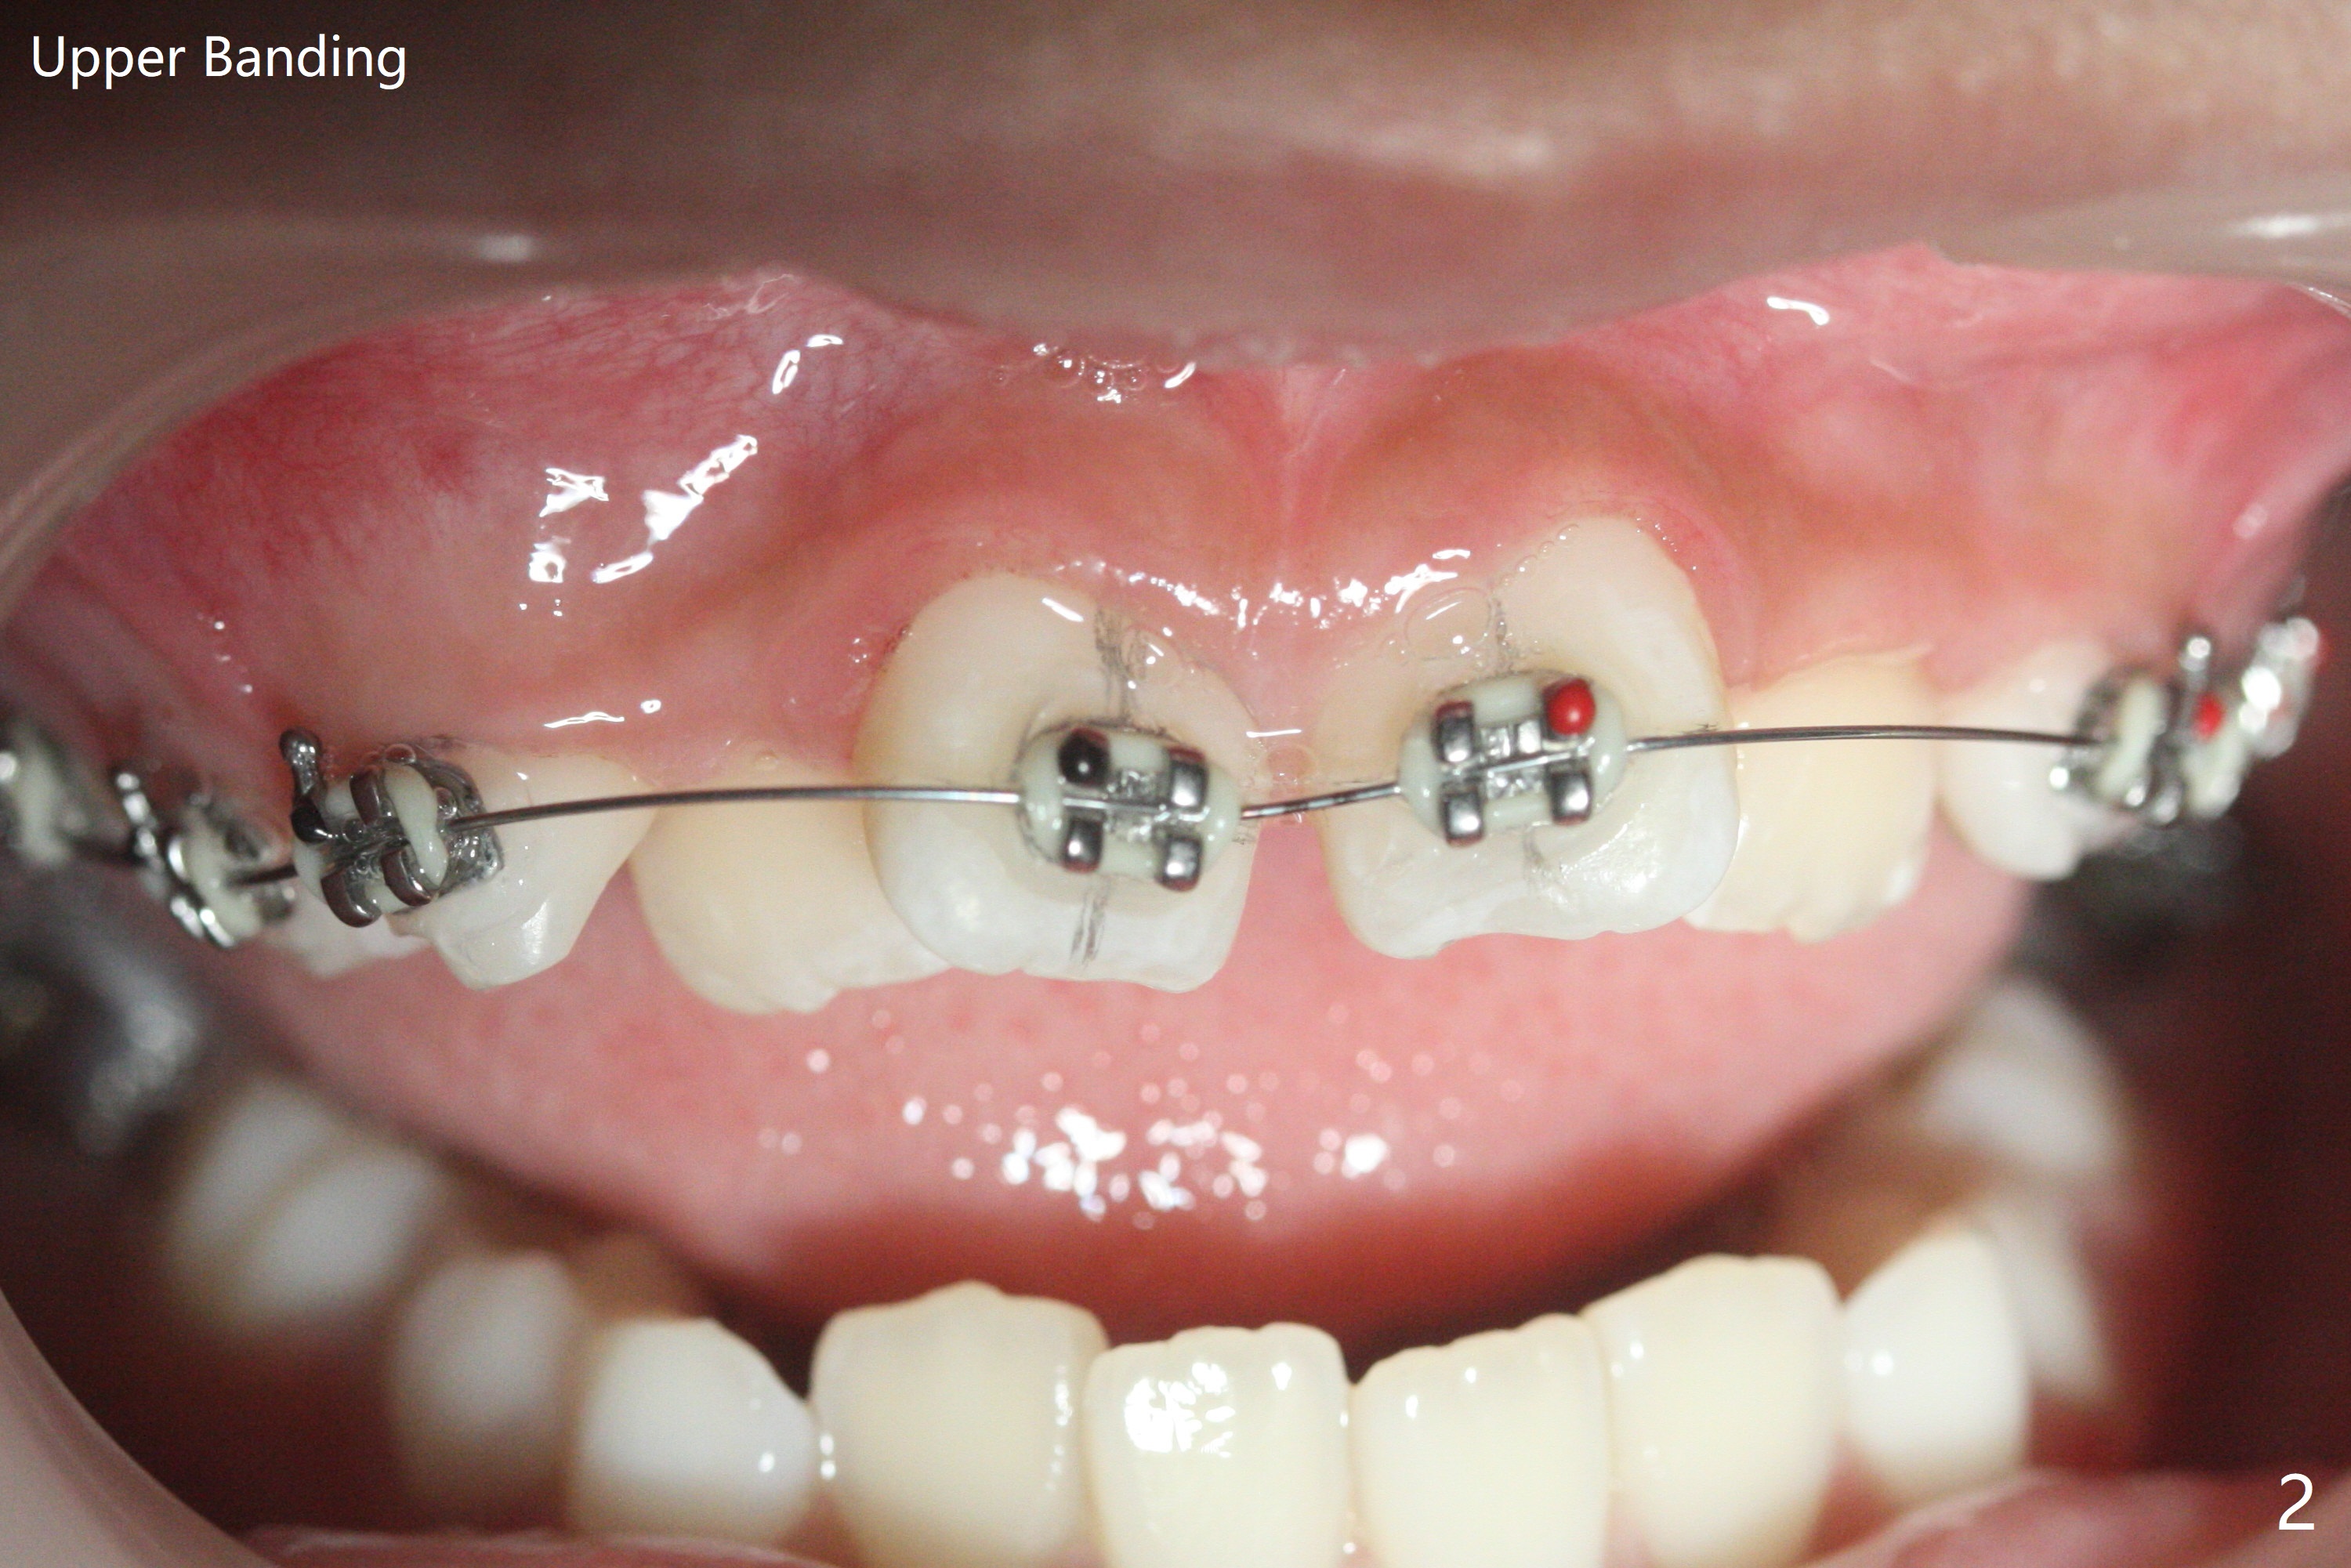

由于上颌拥挤严重,先放置矫正器(图一至三(.012));右上2空间小,可能需要从4近中片切获得,右边open coil spring应该比左边长。